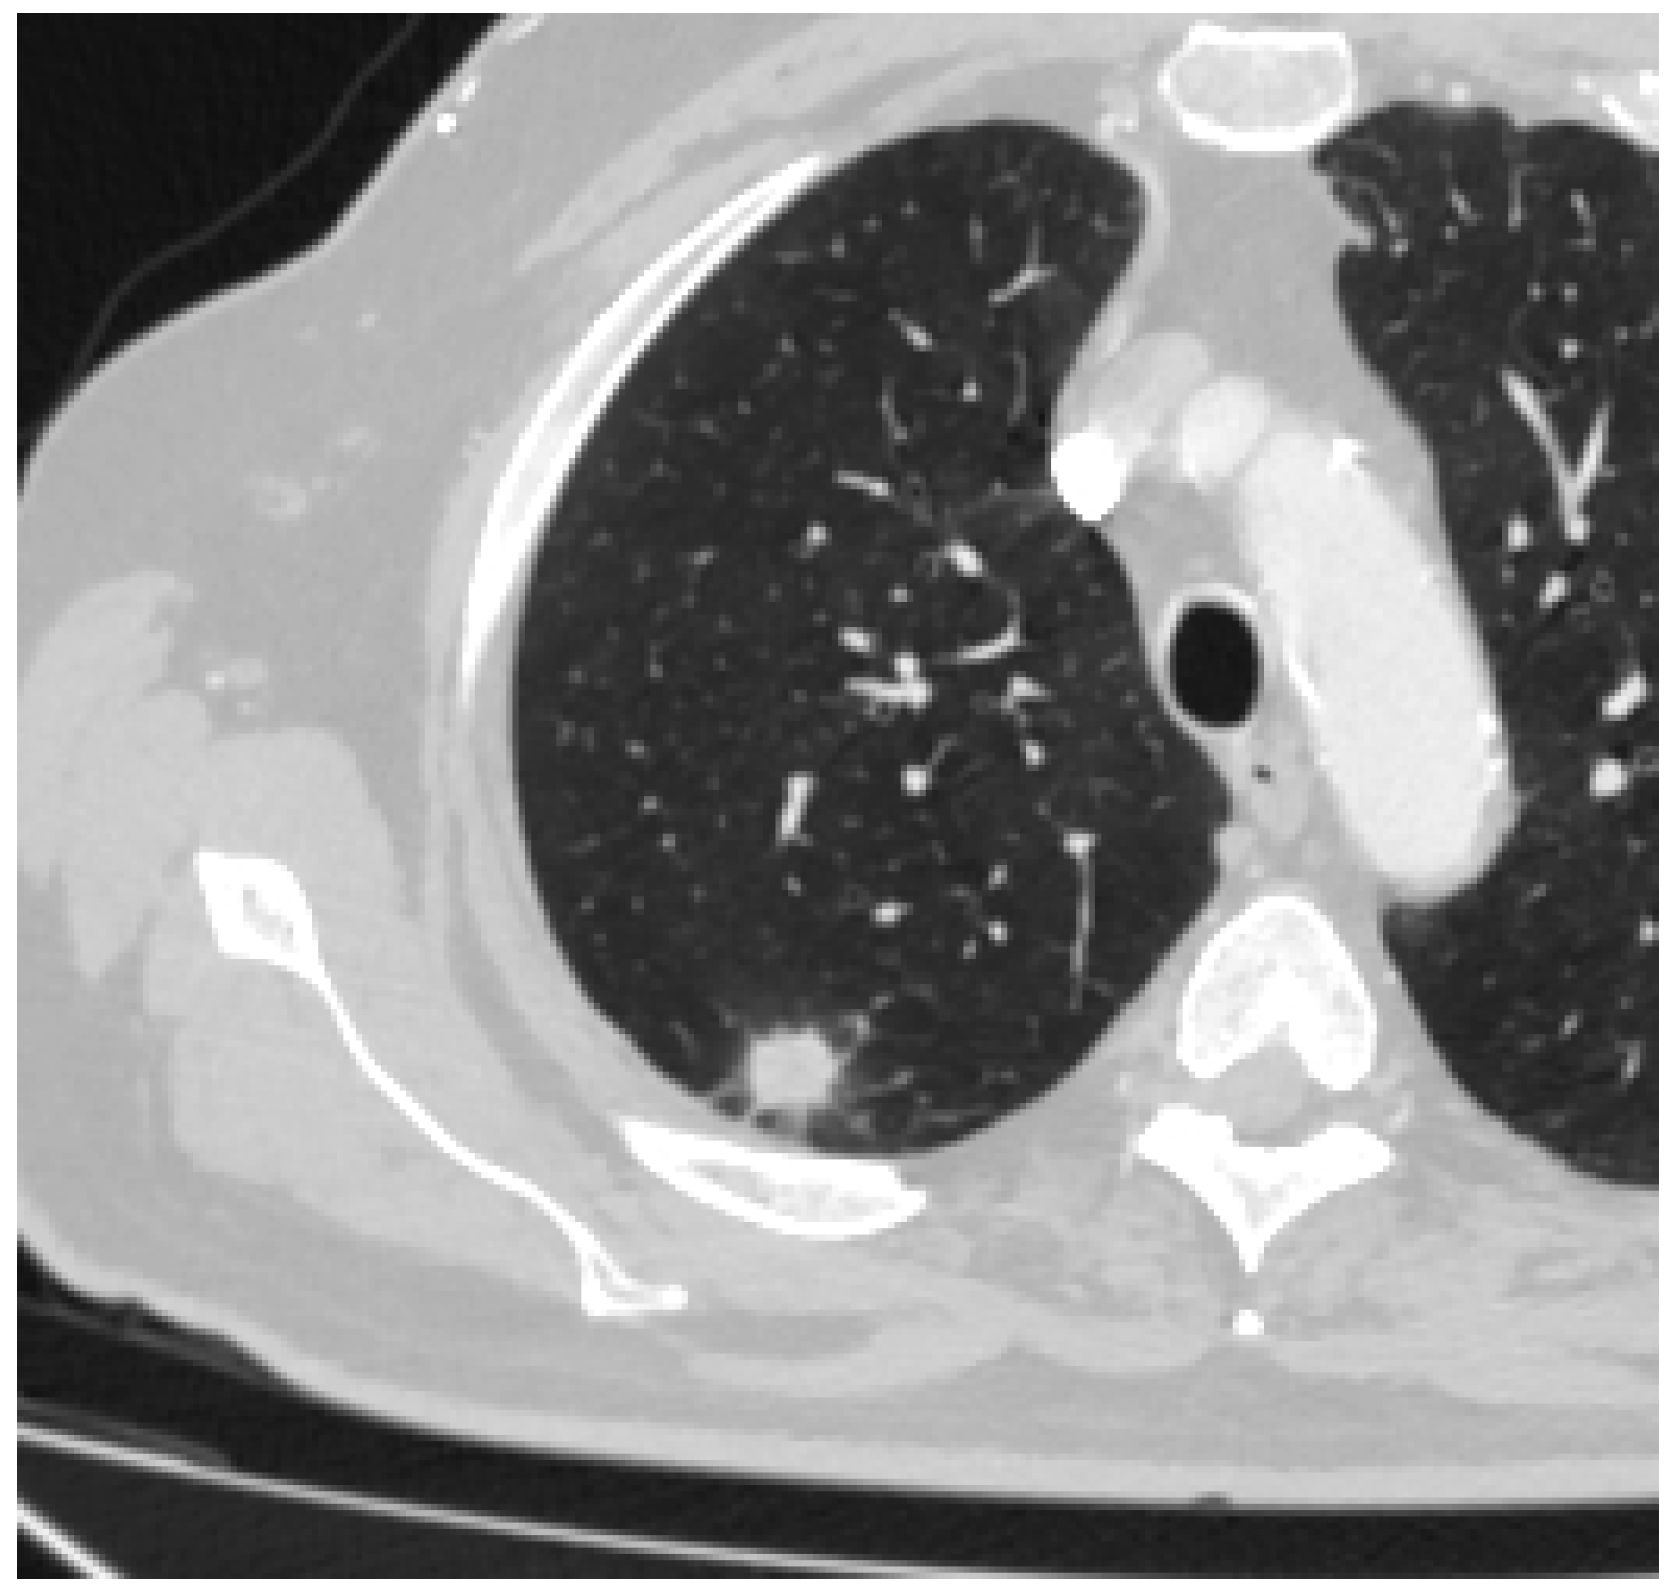

3. Results